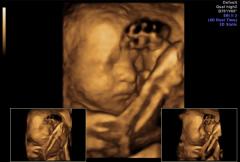

“Ecograful Voluson E8 Expert utilizează o tehnică revoluţionară numită HD live, care atenuează umbrele şi oferă astfel imagini suprinzător de realiste ale fătului. Au trecut vremurile în care medicul le arată parinţilor pe ecranul ecrografului unde este bebeluşul. Acum, parinţii pot distinge singuri chiar şi zâmbetul copilului” – spune dr. Elena Claudia Teodorescu, fondator Donna Medical Center.

Ecograful Voluson E8 Expert, lider în materie de ecografe pentru monitorizarea sarcinii, dotat cu cea mai avansată tehnologie 3D/4D, reprezintă un mare pas înainte în domeniul îngrijirii prenatale: el permite analiza unor informaţii anatomice care nu puteau fi observate până acum.

Cu ajutorul acestui ecograf, la Donna Medical Center atât medicii, cât şi viitoarele mame pot observa imagini 3D şi 4D extrem de realiste ale bebeluşului, surprinse în timp real.